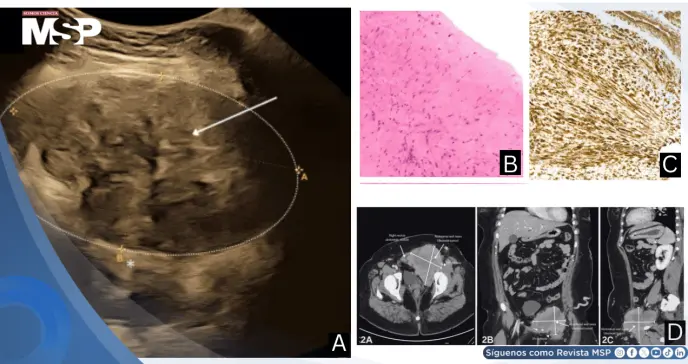

El examen ultrasonográfico demostró una masa heterogénea considerable en la pared abdominal izquierda que medía 10.7 por 6.5 por 10.6 centímetros. La lesión se originaba en el músculo recto abdominal izquierdo con posible extensión hacia el lado contralateral en su porción inferior, sin evidencia macroscópica de invasión intraperitoneal. Los estudios Doppler venosos confirmaron la presencia de trombosis venosa profunda crónica extensa desde la vena ilíaca izquierda hasta la vena poplítea.

La biopsia guiada por ultrasonido proporcionó el diagnóstico histopatológico definitivo. El análisis microscópico con tinción de hematoxilina y eosina reveló una lesión mal circunscrita compuesta por células fusiformes con núcleos alargados y cromatina fina, organizadas en fascículos entrelazados dentro de un estroma colagenoso abundante.

Se observaron figuras mitóticas escasas sin evidencia de atipia citológica significativa ni necrosis tumoral. El estudio inmunohistoquímico demostró positividad citoplasmática difusa e intensa para vimentina en todas las células tumorales fusiformes, hallazgo compatible con el diagnóstico de fibromatosis tipo desmoide.